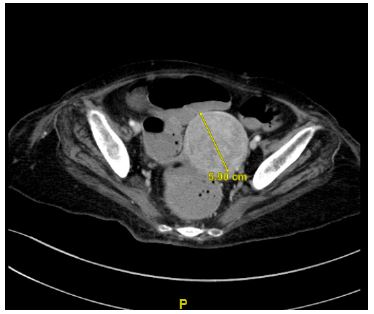

The clinical photograph (Figure 1) depicts multiple warty, raised lesions with a ‘stuck-on’ appearance, on the patient’s back. She had a history of a previous spinal cord tumor. A serum CA-125 was raised, and a Computed Tomography scan found a suspicious-looking heterogenous 5.9 cm uterine mass corresponding histologically to endometrial cancer (Figures 2 & 3).

Figure 2: Axial CT of the patient’s pelvis showing 5.9 cm heterogenous uterine mass.